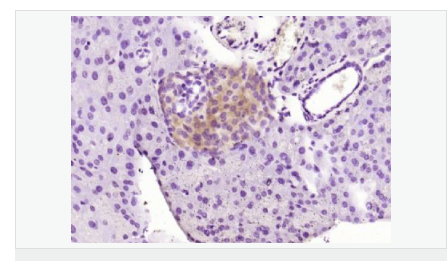

| 產(chǎn)品應用 | WB=1:500-2000 ELISA=1:5000-10000 IHC-P=1:100-500 IHC-F=1:100-500 IF=1:100-500 (石蠟切片需做抗原修復) not yet tested in other applications. optimal dilutions/concentrations should be determined by the end user. |